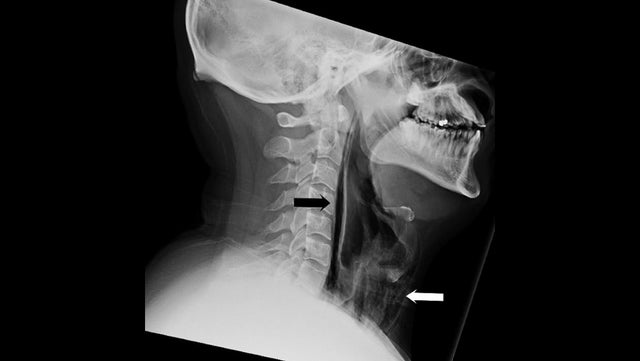

The 34-year-old man came to the emergency room at the University Hospitals of Leicester with painful swelling in his neck and a change in his voice after a forceful sneeze.

He described a "popping sensation" in his neck and said the swelling began "after he tried to halt a sneeze by pinching the nose and holding his mouth closed," the doctors write.

They discovered air bubbles in his neck and chest and determined that the stifled sneeze had torn a hole in the lower part of his throat.